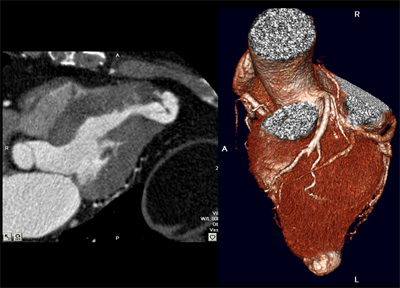

Ventriculograma izquierdo por TC multicorte. Cavidad ventricular en reloj de arena, aneurisma apical de cuello angosto. El diagnóstico diferencial con el pseudoaneurisma ventricular es dificultoso.